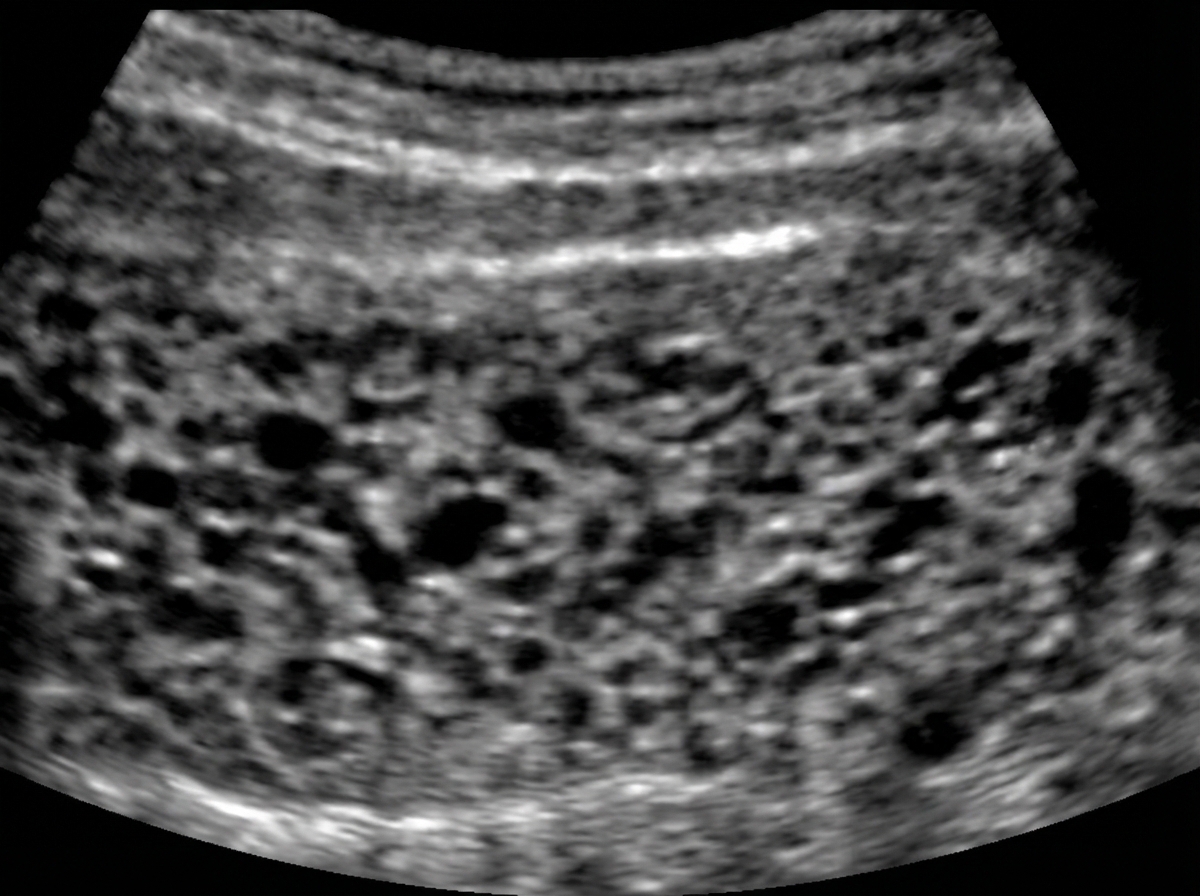

A 30-year-old woman comes to the primary care physician because she has felt nauseous and fatigued for 3 weeks. Menses occur at irregular 24- to 33-day intervals and last for 4–6 days. Her last menstrual period was 7 weeks ago. Her temperature is 37°C (98.6°F), pulse is 95/min, and blood pressure is 100/70 mm Hg. Pelvic examination shows an enlarged uterus. Her serum β-hCG concentration is 96,000 mIU/mL (N < 5). An abdominal ultrasound is shown. Which of the following is the most likely diagnosis?